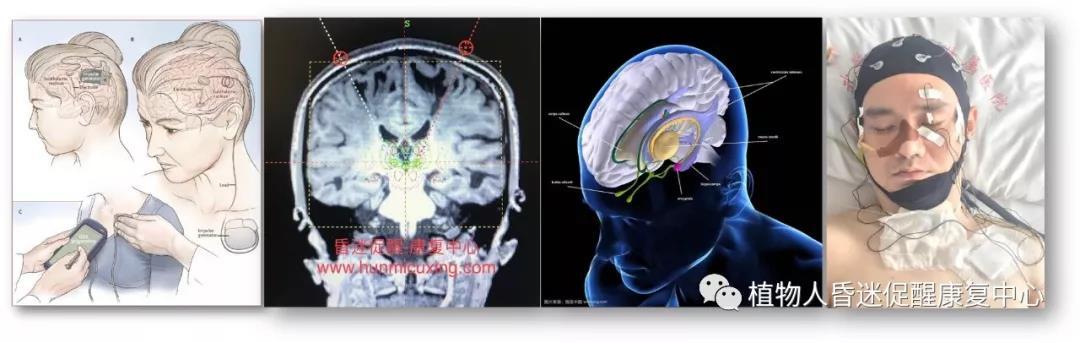

***、脑深部电刺激(DBS):又称为“脑起搏器”,通过植入大脑中的电极发放不同频率的电刺激到控制大脑中的相关神经核团,促进患者清醒。

图4:脑深部电刺激昏迷促醒治疗术中刺激靶点选择和术后脑电图监控调试。

国外自上个世纪80年代即尝试应用 DBS 促醒最小意识状态(MCS)以及持续性植物状态患者的临床研究。刺激的靶点多选择脑干网状结构,基底节和丘脑的板内核(丘脑中央中核-束旁核复合体),这些结构能够弥漫性的兴奋大脑,促进患者恢复意识。

图8:迷走神经刺激示意图。